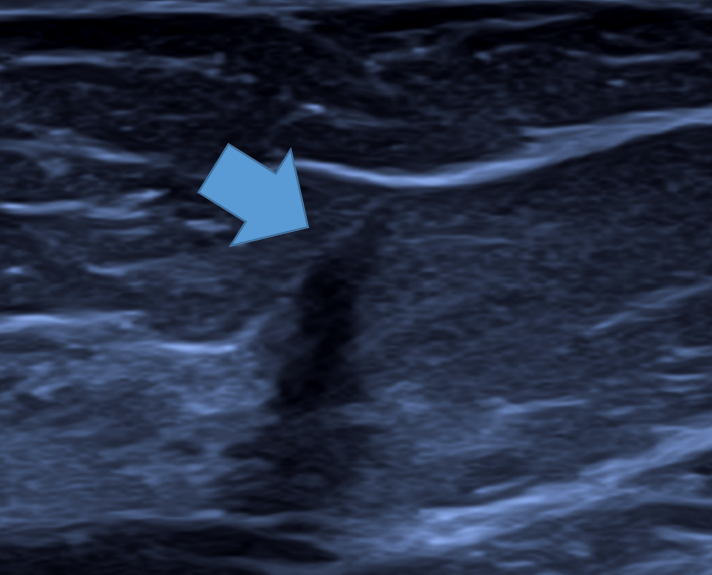

Os ductos mamários apresentam-se à ultrassonografia como estruturas lineares hipoecoicas a isoecoicas, com disposição radial a partir da papila, semelhante aos raios de uma roda. Próximo à papila, seguem um trajeto mais vertical (ântero-posterior), tornando-se progressivamente mais horizontais à medida que se afastam.

O aspecto sonográfico dos ductos é altamente variável e depende principalmente da quantidade de estroma periductal frouxo fibroelástico, do grau de distensão luminal por secreções e da ecogenicidade desse conteúdo. Esse estroma periductal, relativamente isoecoico, pode aumentar o tamanho aparente do ducto, fazendo com que pareça maior do que seu lúmen real.

Em condições ideais, a parede ductal pode ser identificada como uma linha ecogênica fina em cortes longitudinais e como um eco central circular ou linear nos cortes transversais, especialmente na ausência de ectasia ductal.